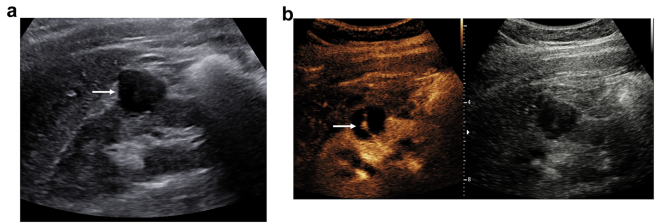

EVAR随访:内漏监测的成本杀手

CEUS对II型内漏的检出率等同CT,81岁患者支架术后3年囊腔扩张仅CEUS捕捉到腰动脉返流